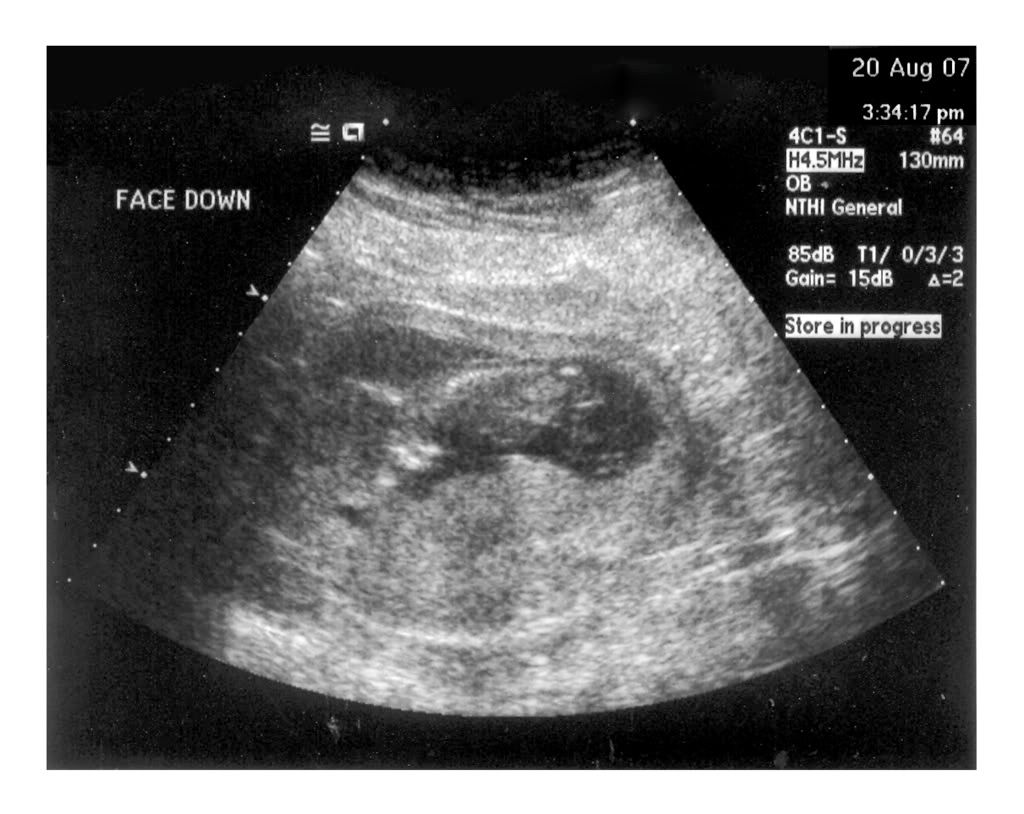

I had my NT test yesterday (8-20) and Chuck and I were able to see and hear the baby. It was a very cool experience to see what actually looked like a baby this time. It was dancing around, waving it's arms and kicking, though it wouldn't cooperate and turn over for the tech. It's hard to see on the picture, but we have a great profile view. The head is on the left, the butt on the right, and it's face down. Click on the photo to see larger image (1024x768).

The heartbeat was 153 beats per minute.